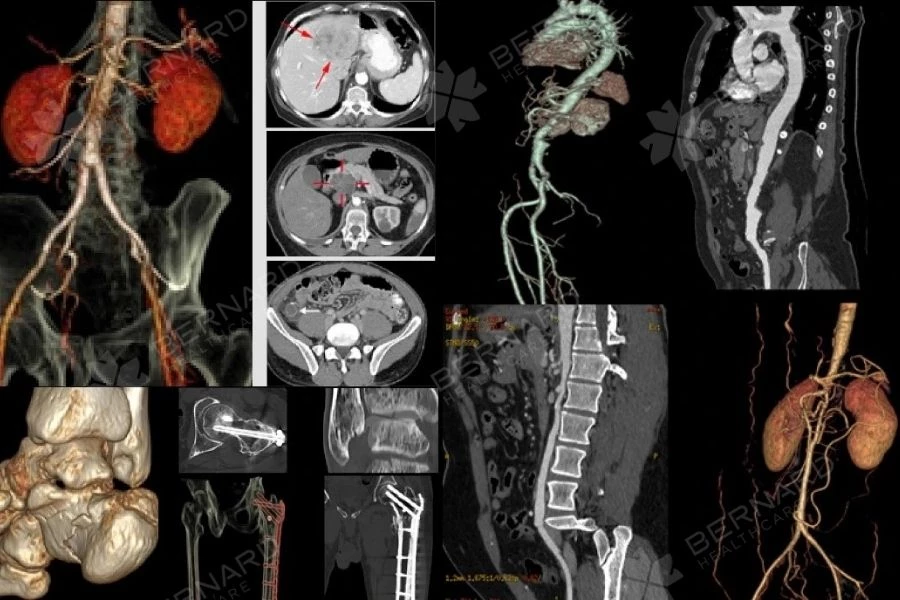

CT Scan bụng – chậu là kỹ thuật chụp cắt lớp vi tính, cho phép khảo sát toàn bộ ổ bụng theo nhiều mặt phẳng khác nhau với độ phân giải cao. Nhờ đó, bác sĩ có thể quan sát rõ cấu trúc các cơ quan như gan, tụy, lách, thận, mạc treo, hệ mạch máu và đường tiêu hóa.

Trong một số trường hợp, thuốc cản quang được sử dụng để làm nổi bật hệ mạch và ranh giới tổn thương. Điều này giúp bác sĩ đánh giá chính xác hơn vị trí, kích thước, hình dạng và mức độ ảnh hưởng của tổn thương đối với các cơ quan xung quanh.

Một trong những ưu điểm nổi bật của CT Scan bụng – chậu là khả năng phát hiện các khối u hoặc tổn thương nằm ở vị trí sâu, khó tiếp cận. Các khối u mạc treo, u sau phúc mạc hoặc tổn thương kích thước nhỏ, chưa gây biến dạng rõ cơ quan thường rất khó quan sát bằng siêu âm.

CT Scan giúp xác định chính xác vị trí, kích thước, ranh giới và mối liên quan của khối u với các cơ quan lân cận, từ đó hỗ trợ bác sĩ định hướng chẩn đoán và theo dõi phù hợp.

Phát hiện các bệnh lý mạch máu ổ bụng

CT Scan bụng – chậu, đặc biệt khi có sử dụng thuốc cản quang, cho phép khảo sát chi tiết hệ thống mạch máu trong ổ bụng. Nhờ đó, bác sĩ có thể phát hiện sớm các tình trạng nguy hiểm như phình mạch, huyết khối, nhồi máu ruột hoặc nhồi máu các tạng trong ổ bụng – những bệnh lý có thể đe dọa tính mạng nếu không được chẩn đoán kịp thời.